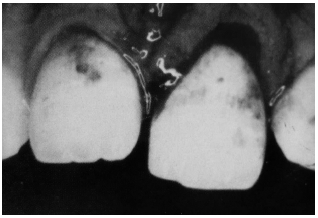

Fractures extending into the dentin are more concerning for pulp necrosis and, therefore, require more aggressive treatment in the the ED. (See Figure 1 and 3.) The risk of pulp necrosis in these patients is 1-7% but the risk increases as treatment time extends beyond 24 hours.3 These patients usually have sensitivity to forced air, percussion, and extremes of temperature. Physical examination reveals the yellow tint of the dentin in contrast to the white hue of the enamel. As the fracture gets closer to the pulp, the dentin develops a slight pink tinge to it. The porous nature of the dentin allows oral flora to pass easily into the pulp chamber, which may result in infection and inflammation of the pulp. This occurs most commonly after 24 hours, but may occur sooner if the fracture is closer to the pulp. Likewise, patients younger than 12 years have a pulp/dentin ratio larger than adults do and, therefore, are at increased risk for pulp contamination. Younger patients should be treated more aggressively and should be seen within 24 hours by their dentist.19

| Figure 3. Dentin |